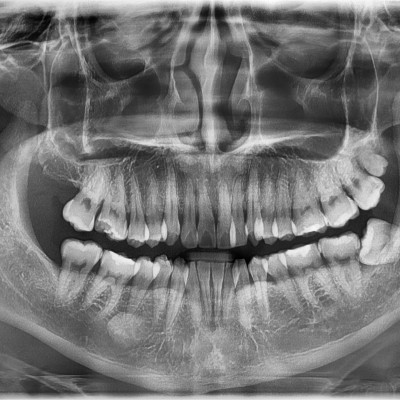

#18,28,38,48 사랑니 발치 #18,28,38,48 사랑니 발치 구강 외과 전문의가 당일 발치했습니다. ------------------..

작성자 이턱이 작성일 02-02 조회 6